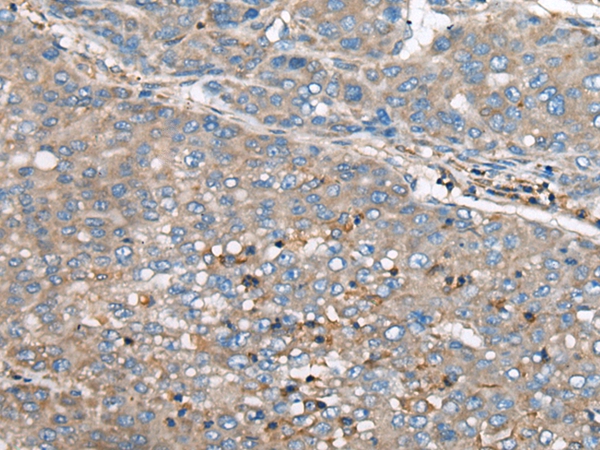

IHC (Immunohistochemistry)

(The image on the left is immunohistochemistry of paraffin-embedded Human liver cancer tissue using 46570(GULP1 Antibody) at dilution 1/65, on the right is treated with synthetic peptide. (Original magnification: x200))